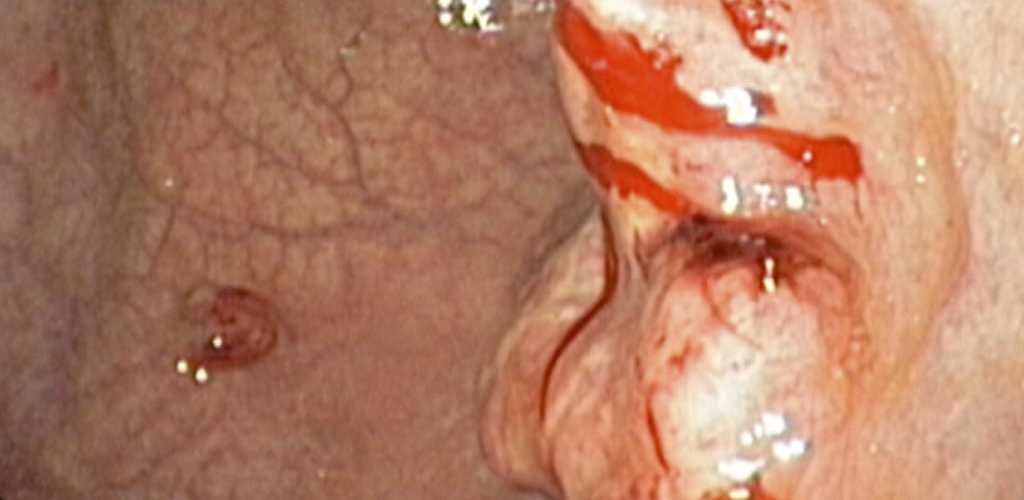

Detección Cáncer Gastrointestinal

El examen que confirma un cáncer gástrico es la endoscopía digestiva alta, procedimiento en que se examina directamente el estómago. El médico al encontrar alguna lesión sospechosa, toma una biopsia para confirmar o descartar el diagnóstico de cáncer. Es muy importante también destacar que ante la presencia de síntomas, aunque sean poco relevantes, es necesario descartar este tipo de tumor, y la única manera de hacerlo es mediante la endoscopía.

Estos síntomas son: dolor quemante en la boca del estómago, hinchazón, disminución del apetito y pérdida de peso sin causa aparente. Más alarmantes son síntomas como vómitos con sangre o deposiciones negras (lo que indica que el tumor está sangrando) o bien síntomas que indiquen que el tumor está obstruyendo el estómago, como vómitos frecuentes o dificultad para tragar.

Ver Imágenes